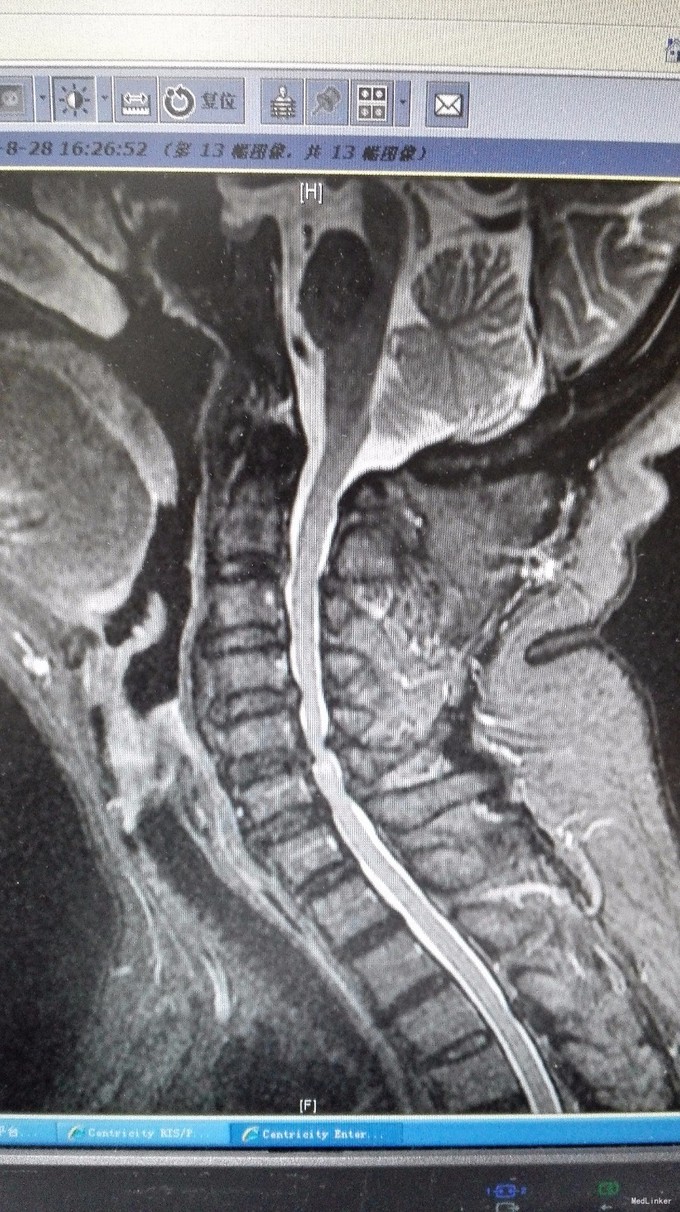

主诉:双手第2、3指尖麻木1年,加重伴双下肢沉重感4月。 病史:1年前出现双手食指、中指指尖麻木,未予以治疗,4月前出现双下肢沉重感,予以腰椎按摩后双下肢症状有所缓解,但双下肢仍有沉重感,右下肢较重,在外院诊治为颈椎病,建议手术治疗,患者拒绝,为求进一步诊治,特来我院就诊,门诊拟混合型颈椎病收入我科住院治疗。

查体:双手麻木感,肱三头肌肌腱反射活跃,左侧髂腰肌4级,臂丛牵拉实验阴性,椎间孔挤压实验阴性。 辅查:CT:C2-7椎间盘突出,继发性椎管狭窄,OPLL,OFL。

诊断:混合型颈椎病(脊髓型+神经根型) 治疗:颈后路3-7单开门椎管扩大成型术(锚定法)